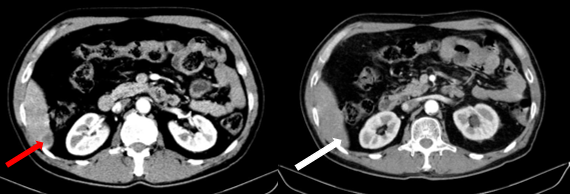

Sau 3 chu kỳ điều trị, bệnh nhân được làm lại các xét nghiệm và chụp lại kiểm tra. Kết quả cho thấy kích thước các khối u đều giảm đáng kể, thẻ hiện sự đáp ứng tốt với liệu trình điều trị của bệnh nhân

Hình 5. Hình ảnh phim chụp cắt lớp vi tính bụng ngày 10 tháng 7 năm 2025 (mũi tên trắng) so với ngày 19 tháng 03 năm 2025 (mũi tên đỏ) cho thấy hình ảnh khối u gan đã gần như biến mất hoàn toàn.